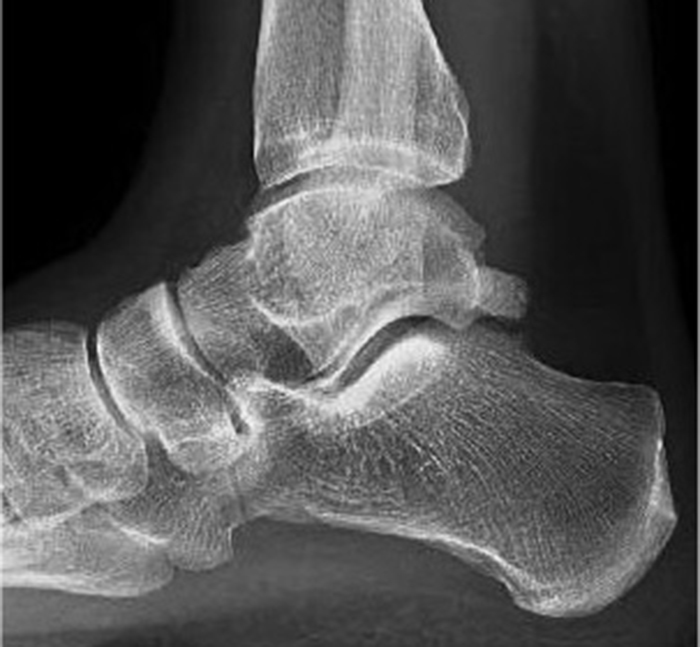

En la imagen mostramos una radiografía lateral en carga de un paciente con limitación a la flexión dorsal del tobillo. El paciente padece el síndrome...